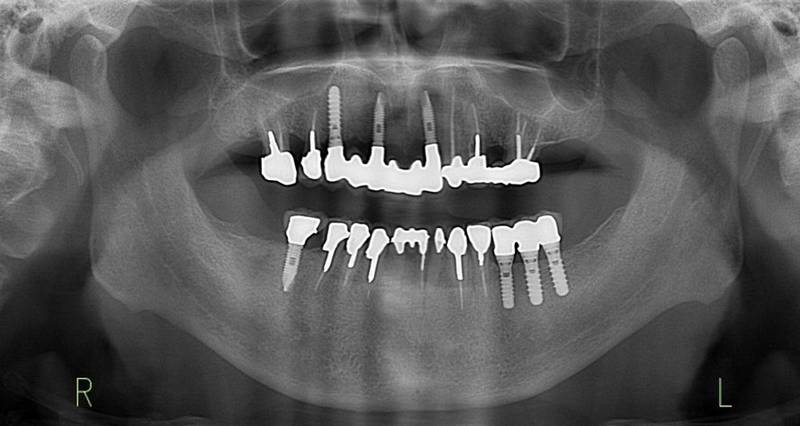

治療後。歯周病で失われた骨が回復しています。使用インプラントはスプラインツイストです。

上部構造装着後6年。ハイブリッドレジンを使用したため、少し艶がなくなってきました。上部構造の材料には金属、ハイブリッドレジン、セラミックなどがあります。セラミックはきれいですが欠けやすいため、最近はフルジルコニアを使っています。

上顎 少しすり減ってきました。

下顎。12か月に一度メインテナンスをしています。

インプラント装着後6年。順調に経過しています。12か月毎のメインテナンスをしています。